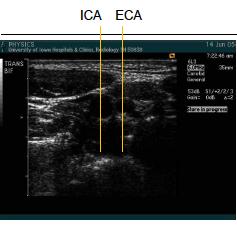

general rules for finding the ICA and ECA

_____ approach, ICA is more often lateral or posterior.

You can tell from the _____ of bifurcation, it will be difficult to get the “Y” view of ICA and ECA together.

If you can not get the “Y” view, you must image each vessel _______.

_____the transducer over the bulb to find the ECA and ICA – see video clip

Lateral

transverse

separately

“Pivot”

From the ______ window you can not get the “Y”.

You will need to image the ICA and ECA separately.

moving to the _____ aproach for the longitudinal images will demonstrate the “Y” view.

anterior